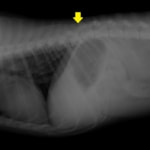

症例:交通事故による椎体脱臼

柴犬:9歳、避妊雌

交通事故直後、胸腰部に激しい疼痛、両後肢に完全麻痺を認め、シェフシェリントン徴候を呈していました。レントゲン検査において、第11-12胸椎間の脱臼が認められました。

脊髄の減圧、脊柱管の再構築・安定化を目的に、片側椎弓切除術およびMatrixMANDIBLE Plateによる椎体固定を実施しました。

隣接椎体を架橋するようにプレートを設置しました。

術後レントゲン写真